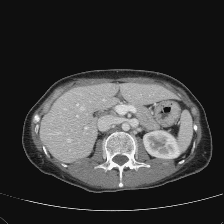

Figure 3 presents a qualitative comparison of segmentation performance on examples from the Synapse, BTCV, ACDC, and ISIC17 datasets. The first two examples (from Synapse) highlight variations in segmentation performance among U-Net, TransUnet, Mamba-Unet, and Swin-Unet. While Swin-Unet performs well in the first example, its performance decreases in the second example, particularly in segmenting the organ highlighted in blue. Additionally, it misclassifies background regions as the class highlighted in orange. In contrast, our approach demonstrates high robustness in segmenting all classes accurately and aligning well with the ground truth masks.

Across BTCV, ACDC, and ISIC17, the comparison methods exhibit varying performance depending on the task and class. For instance, Mamba-Unet struggles to segment multiple organs in BTCV, even misclassifying certain classes as others. In the ACDC dataset, both TransUnet and Mamba-Unet perform poorly in segmenting the three classes. In the last column (ISIC17), Swin-Unet oversegments the skin lesion compared to the ground truth. Unlike the comparison models, our approach consistently delivers effective segmentation across different tasks and datasets.

These qualitative findings further reinforce the quantitative results presented in the experimental section, demonstrating the effectiveness of our MambaCAFU model in handling binary and multi-class segmentation across diverse medical imaging modalities and tasks.

Slice GT Unet TransUnet Mamba-Unet Swin-UMamba MambaCAFU-V1

Figure 3: Visual comparison of segmentation examples from Synapse (first two examples), BTCV (3-4 examples), ACDC (5th example) and ISIC17 (last example). Columns: input slice, ground truth, Unet, TransUnet, Mamba-Unet, Swin-UMamba, and MambaCAFU-V1.